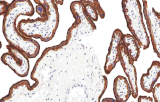

- Linfoma follicolare: tipici pattern di co-espressione (es. CD10 con BCL2 aberrante).

- Linfoma a cellule mantellari: ciclina D1 e SOX11 come marcatori chiave, incluso supporto per i casi ciclina D1 negativi.